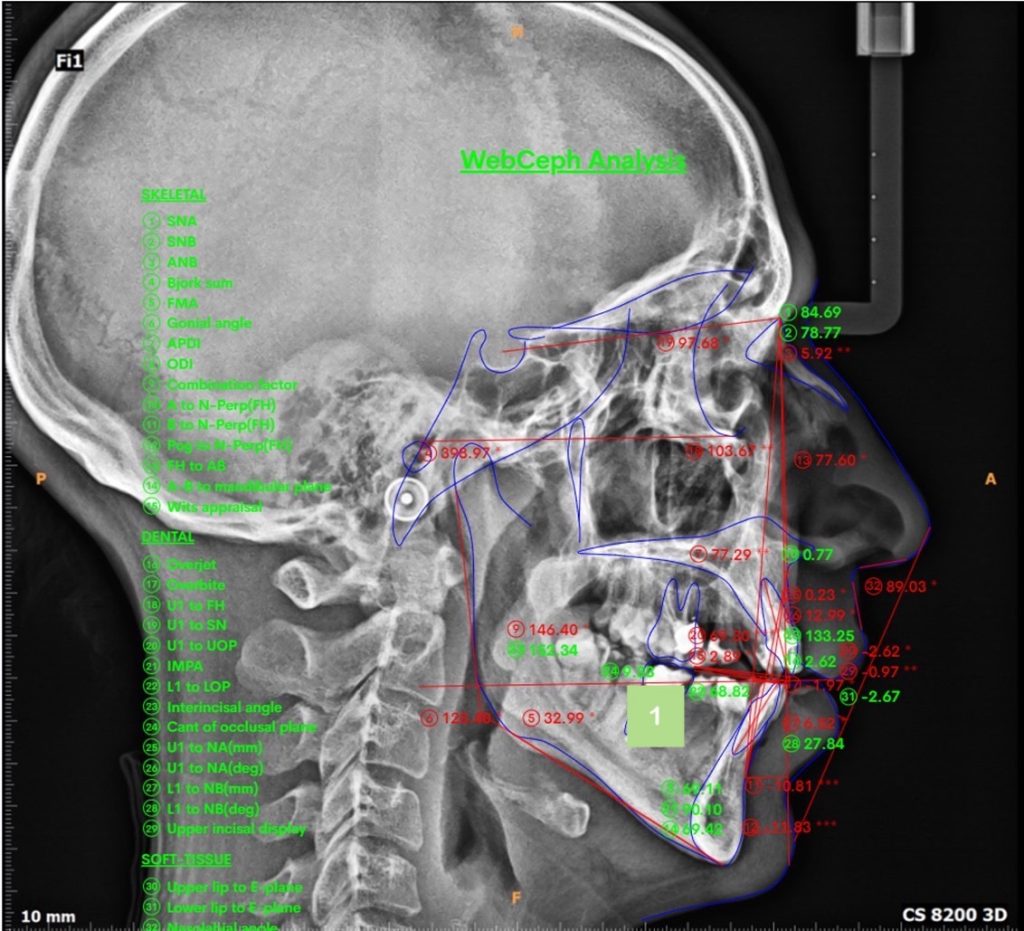

By the help of cephalometric analysis, the patient diagnosed as “Skeletal Class II”; Due to retuded mandible ( SNA= 84, SNB= 78, ANB= 5.92)

The patient suffered from Skeletal midline shift (due to improper position of the mandible) which requires invasive intentional endodontic treatment to the lower six incisors to correct the midline shift (It's better to be conservative rather than devitalization as lower midlineshift is not an esthetic concern).

More than 2 mm midline shift